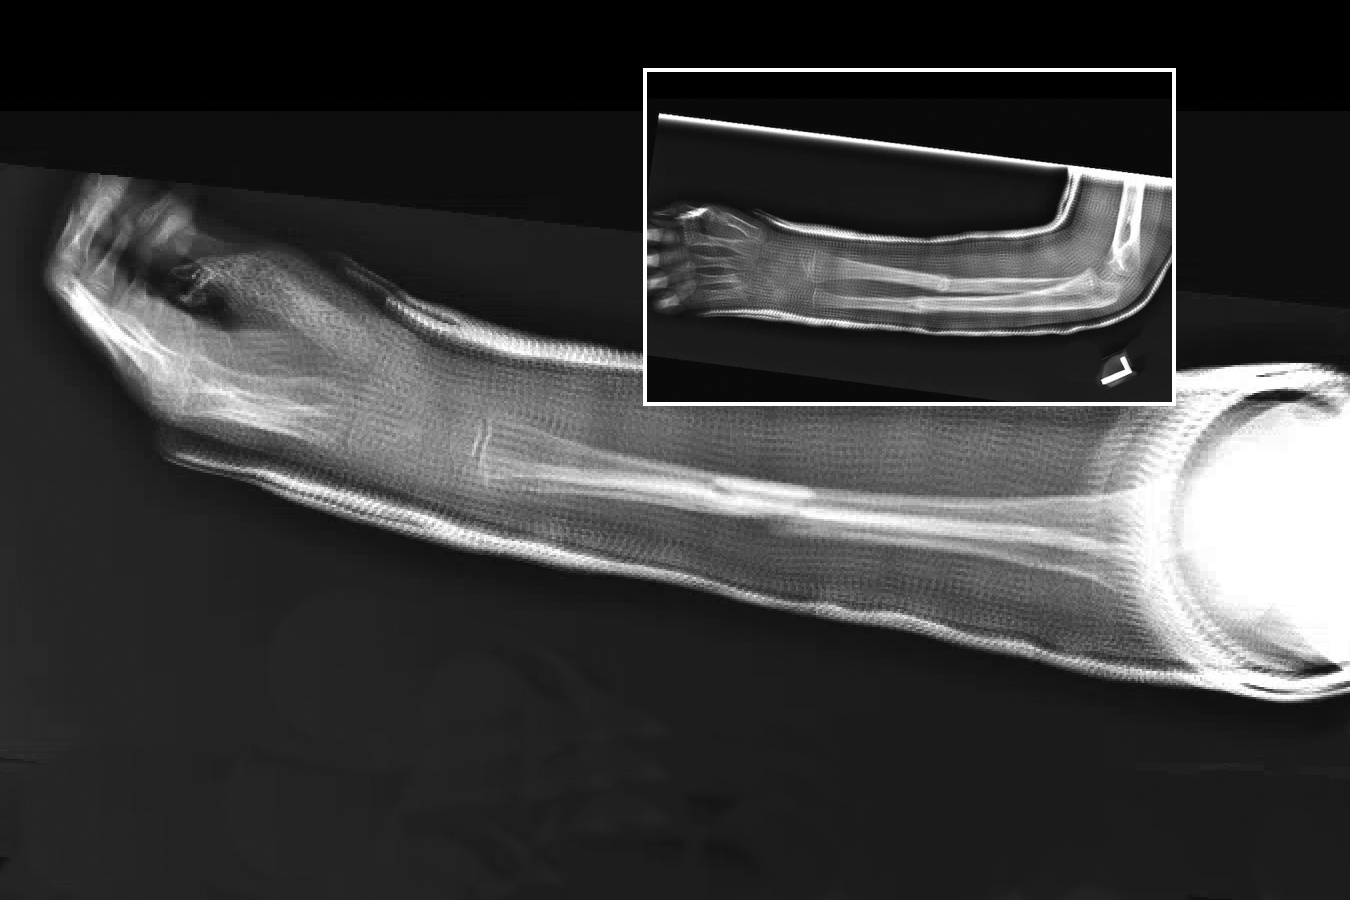

Forearm shaft fractures are the most common fracture type in the pediatric population. Although either the radial shaft or ulnar shaft can be fractured in isolation, both bones are usually injured simultaneously, which is referred to as a “both bone” forearm fracture. Males between the ages of 9-12 are at the greatest risk for forearm fractures, and the mechanism of injury usually involves indirect trauma, such as a fall on an outstretched arm (FOOSH) with a rotational component. Most pediatric patients are treated conservatively with closed reduction and immobilization, although surgical intervention may be indicated for those that fall out of specific parameters for acceptable alignment after reduction. The rate of surgery has also been increasing in recent years.1-4,28